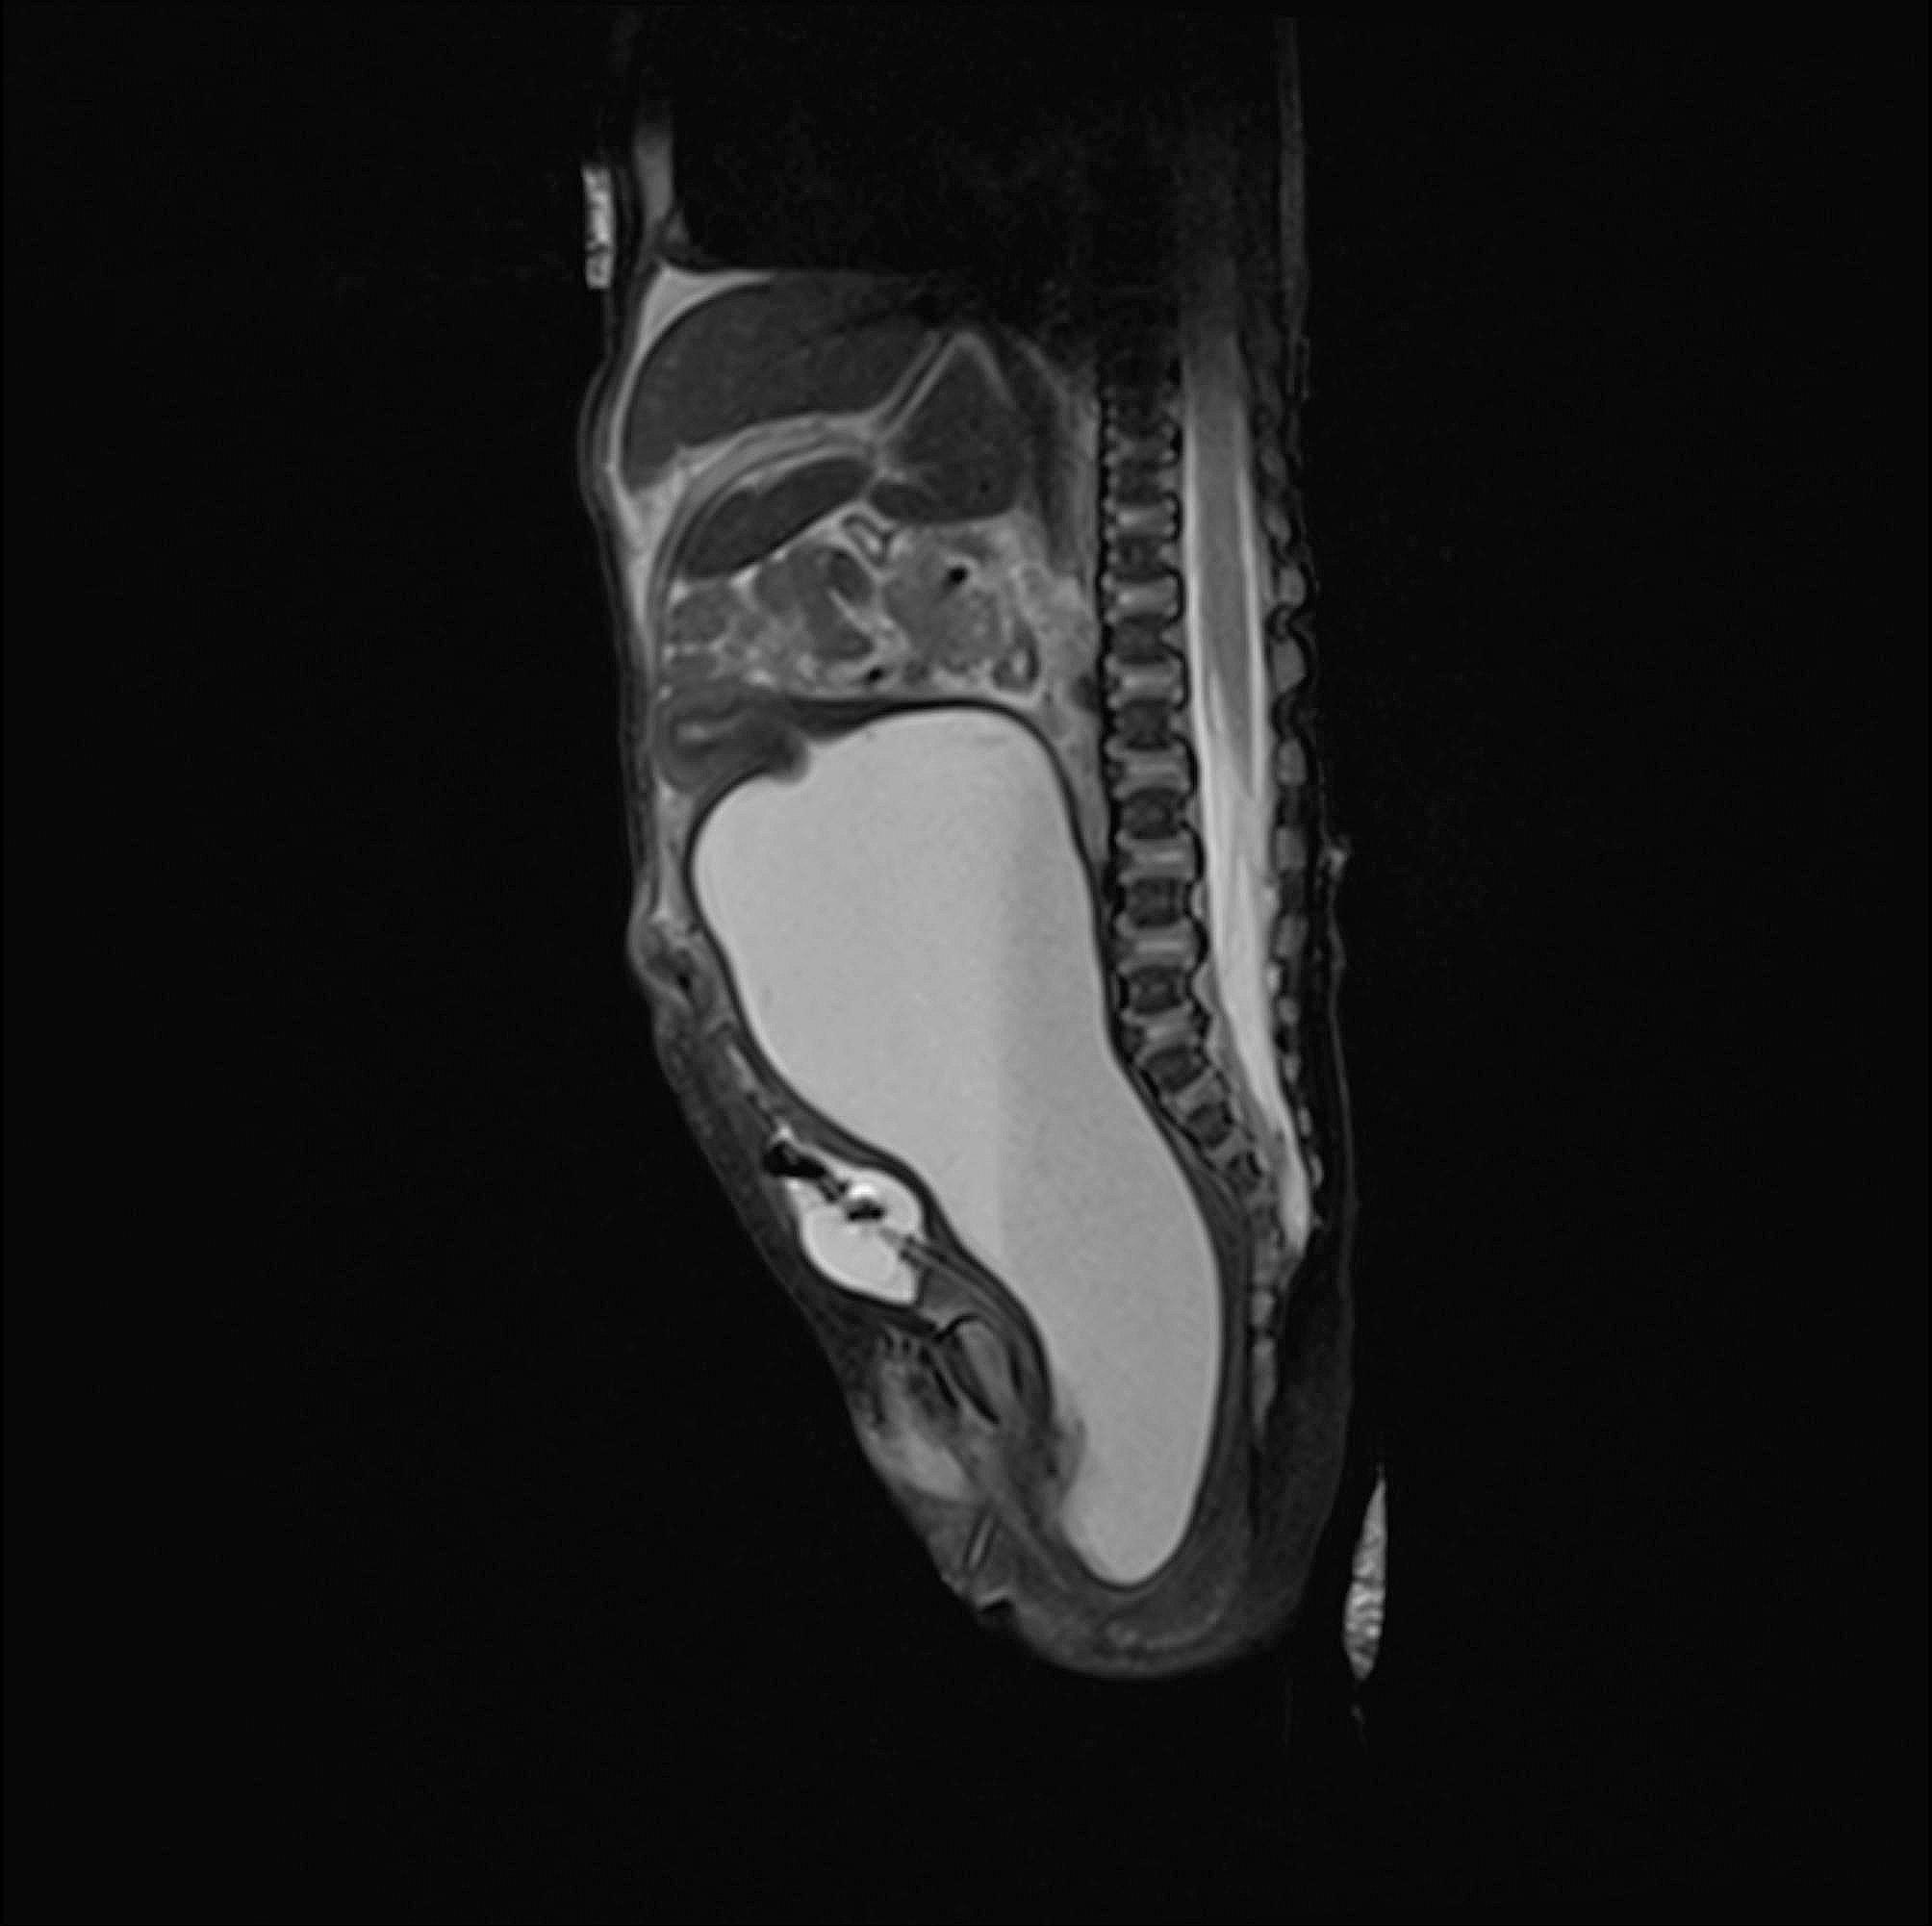

Case presentation: We present here the case of a preterm neonate who was admitted to the surgical neonatal intensive care unit for bowel obstruction. The baby did not appear septic or unwell, a small amount of meconium passed frequently, and no bilious gastric residuals occurred. Based on these findings, acute abdominal obstruction was doubtful, and the surgeon chose a conservative (watch and wait) approach. Subsequently, we performed abdominal ultrasound and magnetic resonance imaging based on unclear information about a suspicious abdominal mass raised by the gynecologist shortly before the emergency C-section. The final diagnosis was congenital hydrocolpos due to imperforate hymen. The pediatric gynecologist indicated an incision of the imperforate hymen under general anesthesia. The incision resolved abdominal distention as well as the bowel obstruction.

Conclusion: The presentation of hydrocolpos was not typical (no bulging in the vaginal introitus) in our case, and clinical symptoms implied acute bowel obstruction shortly after birth. The surgeon chose a conservative (watch and wait) approach as the baby did not appear unwell on the second day of life. Fortunately, diagnostic laparotomy was not required as the next step in bowel obstruction management. All clinical symptoms resolved after a minor surgical procedure.